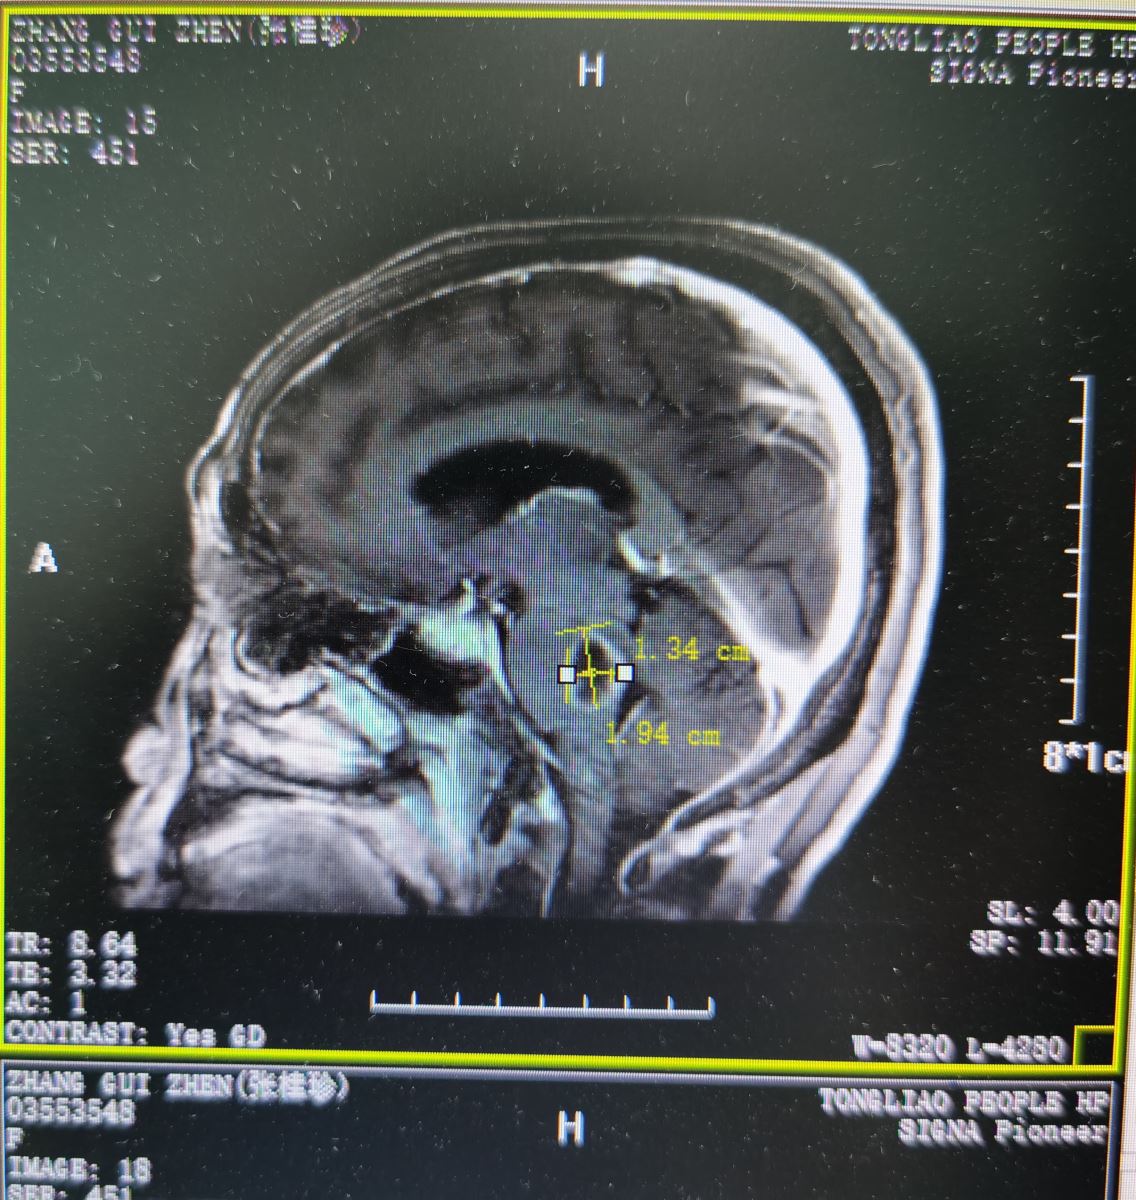

张某,女性,68岁,患者来我院就诊前3天出现无诱因间断性头晕、恶心、复视,偶有出现回答错误,走路不稳并向右侧偏等症状。在当地医院进行相关检查,头颅MRI(颅脑核磁共振)检查提示为脑桥囊性占位。为进一步诊治来我院就诊。查体:该患者左眼轻度外展,右侧肢体肌力4+级,精细动作差,病理反射阴性。头颅MRI增强扫描,结果提示为脑干肿瘤,收入我院东院区神经外科。